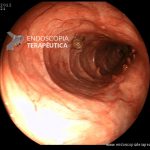

- Doença de Crohn em remissão – cicatriz